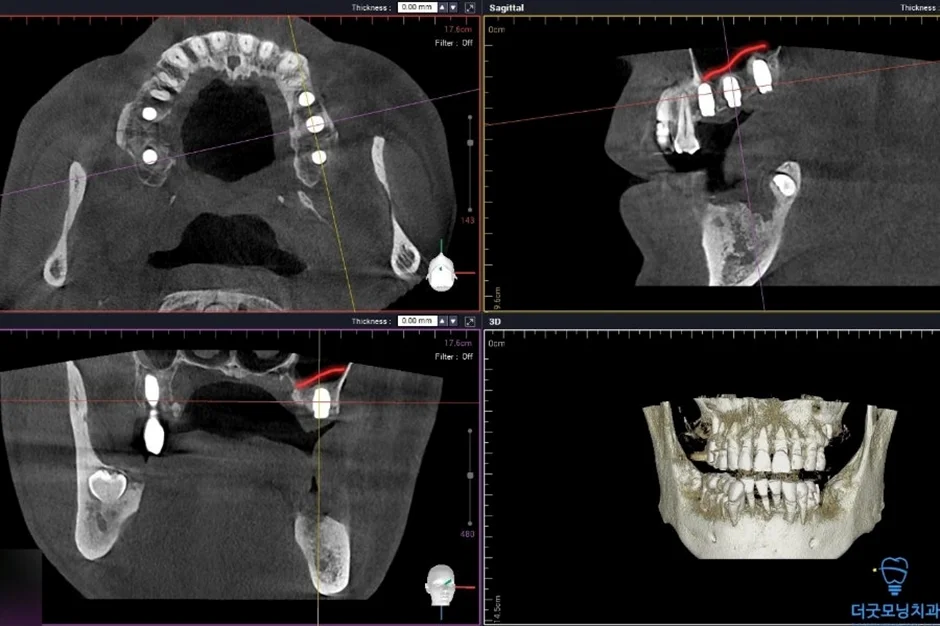

■ 2차 수술 (왼쪽)

환자분이 충분히 회복하신 이후 반대쪽도 동일하게 수면치료로 진행하였습니다.

노란색 표시처럼 임플란트 식립 잘 마쳤습니다.

두 번째 수술에서도 임플란트가 CT 상에서 확인될 만큼 정확하고 안정적으로 식립되었습니다.